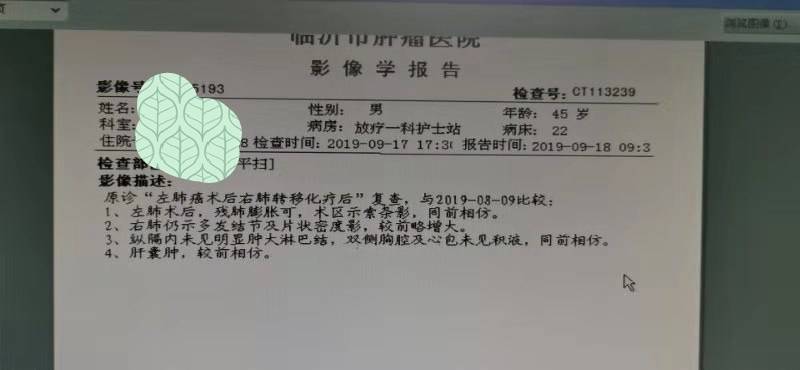

战战兢兢走过三年多点,这次复查有变化,化疗实在是不想再用了,老公身体状况很好和正常人一样,只是身体里有个不老实的总是反反复复折磨着人。16年5月份左肺下页手术,一年后复发,基因检测两次都是阴性,易瑞沙也盲试过无效 ,只能一直化疗,身体不耐受了就赶快停下来养精蓄锐,本来期待能老老实实的安稳两三年,哪想到复查七月份复查又有变化,盲吃了克唑替尼一个月也是无效。8月份右肺穿刺重新做检测,这次我们是幸运儿,有新突变但是不知道先用哪种好?